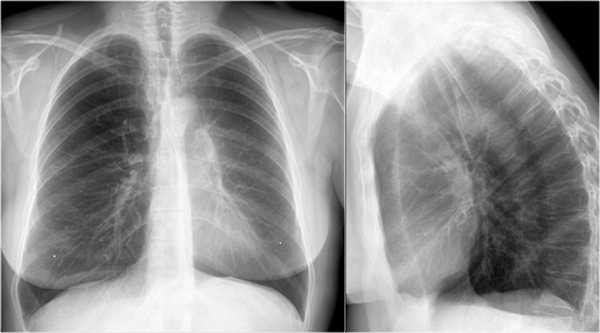

Ателектаз средней доли правого легкого.

- Симптом силуэта — нечеткие границы правых отделов сердца.

- Трехгранные изменения высокой плотности, визуализирующиеся на боковой рентгенограмме, являются результатом ателектаза средней доли правого легкого.

При ателектазе средней доли правого легкого подъем диафрагмы навсегда значительно выражен.

Ателектаз нижней доли правого легкого.

На нижепредставленой рентгенограмме пациента 70 лет, упавшего с лестницы, в плевральной полости определяется скопление жидкости, предположительно являющейся кровью.

Это ателектаз нижней доли правого легкого.

Обратите внимание на правую границу сердца. Правая междолевая артерия не видна потому, как она не окружена воздушной легочной тканью, а закрыта спавшейся нижней долей правого легкого.

Ниже представлены последующие рентгенограммы органов грудной полости того же пациента, на которых ателектаз разрешен.

Обратите внимание на правую междолевую артерию (красная стрелка) и границы правых отделов сердца (синяя стрелка).